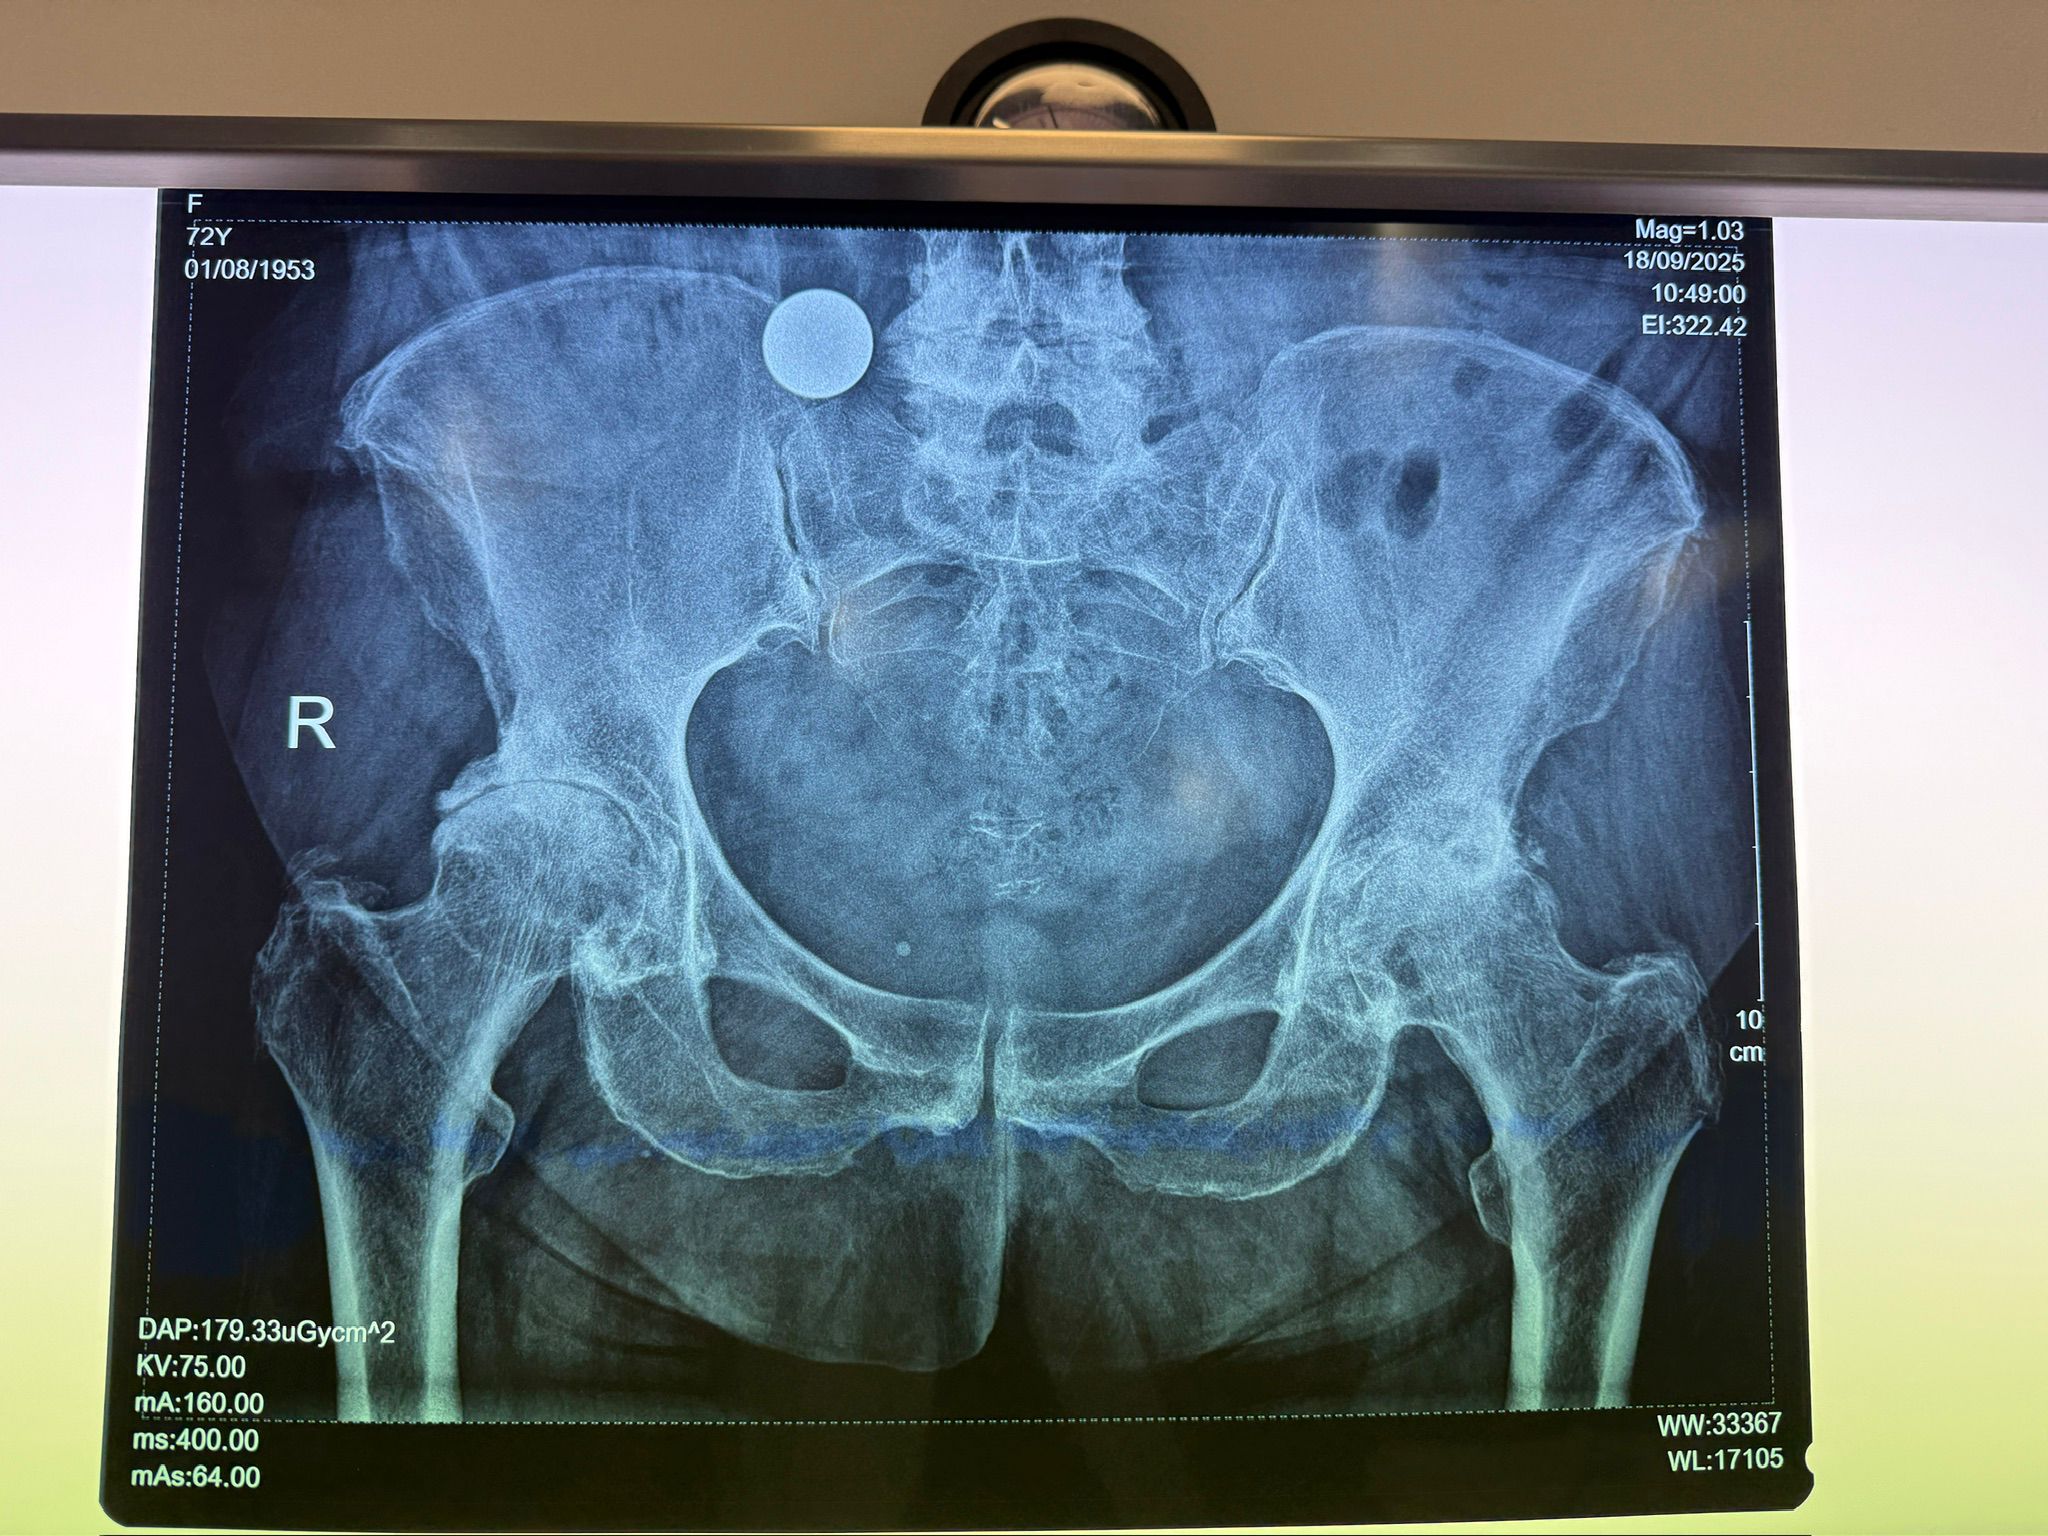

Imagini Clinice